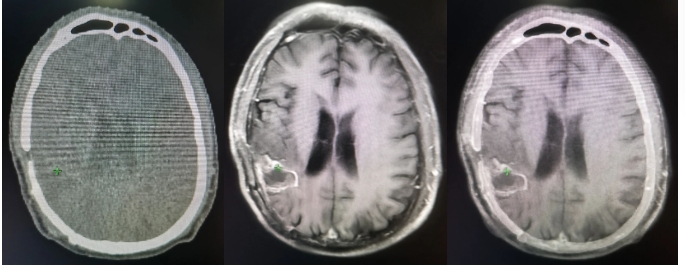

首先需要将定位的CT图像上传到放疗专用的计划系统里面。有时候对于特殊部位的肿瘤,为了更准确的显示病灶,除了CT图像以外,可能还需要用到MRI、PET等影像,将定位CT图像与MRI或PET/CT图像进行融合,这也是很耗时间的。有时候为了匹配更精准,可能需要连续几个小时的处理。这个步骤需要放疗物理师来完成的。

图像处理完成后,就需要放疗医师进行靶区和危及器官的勾画。靶区也就是做放疗需要照射的区域,危及器官是需要保护的靶区周围的正常器官,这些都需要反复斟酌,非常谨慎的勾画。通常情况下由主管医生勾画,画好以后需要高年资的放疗医师再次审核,对于疑难的靶区还需要放疗医生和影像科医生共同讨论,层层把关,并且在放疗申请单上签字确认,保证放疗靶区的准确性。这个过程复杂,并且耗时较长。